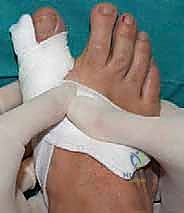

تقنية SERI (Simple, Effective, Rapid, Inexpensive) التي يتقنها ويطبقها الأستاذ الدكتور محمد هطيف بنجاح باهر، هي تقنية جراحية مبتكرة تعتمد على إجراء تصحيح عظمي (Osteotomy) لعنق عظمة المشط الأول من خلال شق جلدي دقيق جداً لا يتجاوز 1 سنتيمتر، وبدون الحاجة إلى كشف المفصل أو تدمير الكبسولة والأربطة المحيطة به.

- المشي الفوري: يمكن للمريض المشي على قدمه (باستخدام حذاء طبي خاص) في نفس يوم العملية أو اليوم التالي مباشرة، وهو أمر مستحيل في الجراحات التقليدية.

- تثبيت بسيط وفعال: يتم تثبيت العظم بعد قصه باستخدام سلك معدني رفيع جداً (K-wire) يتم إزالته لاحقاً في العيادة بدون ألم، دون الحاجة لترك مسامير دائمة داخل جسم المريض.